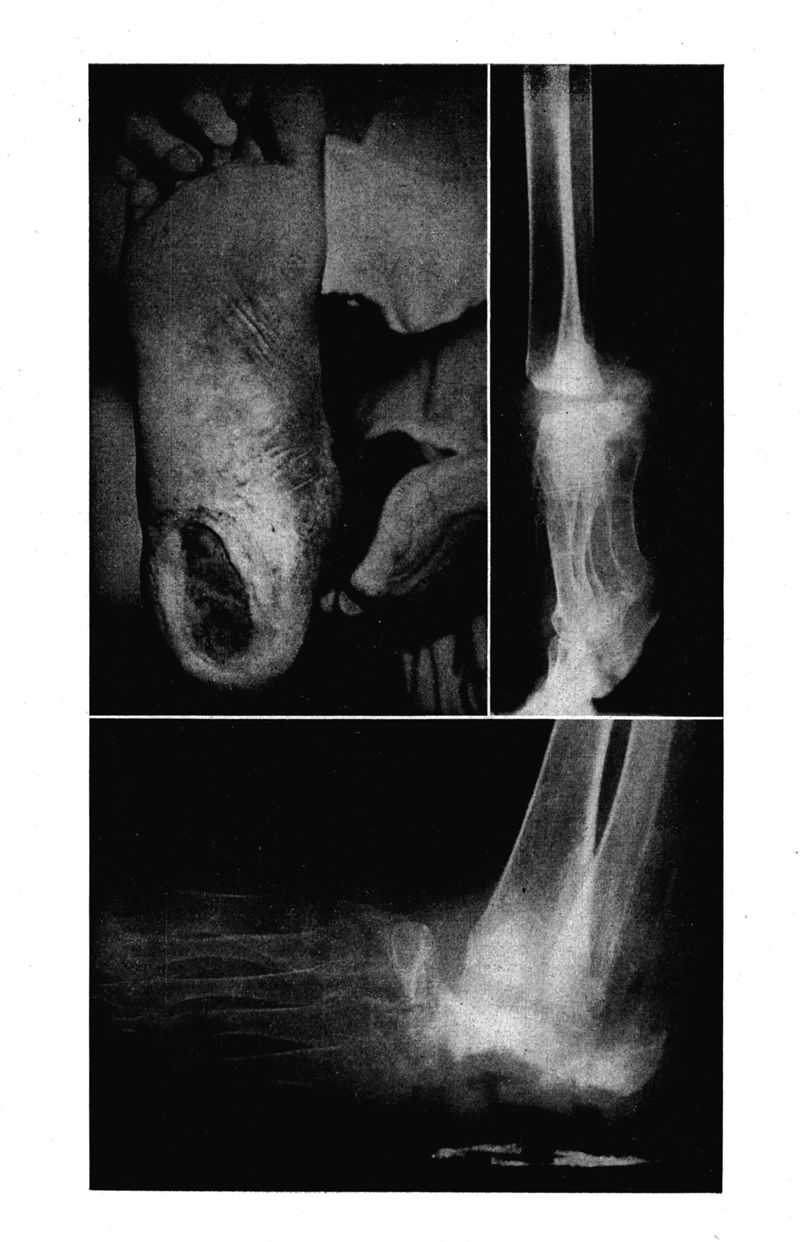

Médecine tropicale : Revue du service de santé des troupes de marine

. - Marseille : Ecole d'application du service de santé des troupes de marine, 1964.